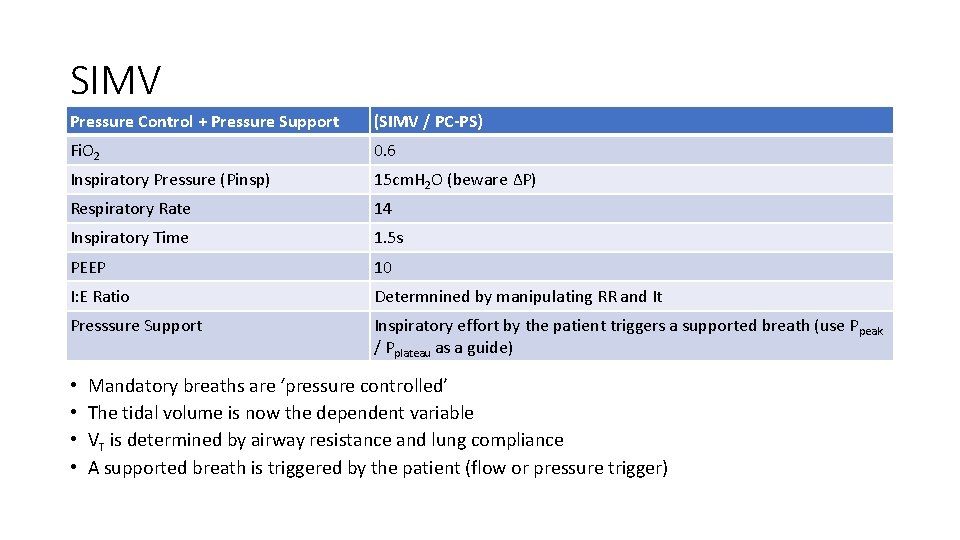

SIMV Pressure Control + Pressure Support (SIMV / PC-PS) Fi. O 2 0. 6 Inspiratory Pressure (Pinsp) 15 cm. H 2 O (beware ∆P) Respiratory Rate 14 Inspiratory Time 1. 5 s PEEP 10 I: E Ratio Determnined by manipulating RR and It Presssure Support Inspiratory effort by the patient triggers a supported breath (use Ppeak / Pplateau as a guide) • • Mandatory breaths are ‘pressure controlled’ The tidal volume is now the dependent variable VT is determined by airway resistance and lung compliance A supported breath is triggered by the patient (flow or pressure trigger)